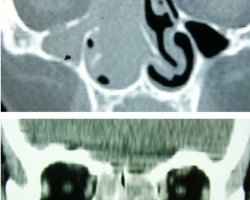

Homme de 70 ans

Epistaxis bilatérale

ATCD : rhinosinusite chronique, menuisier pdt 40 ans, tabagisme

Depuis 2 mois : mouchage sanglant + obstruction nasale droite